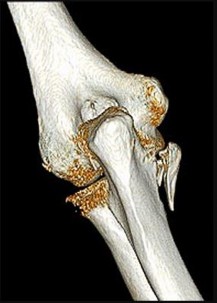

A 55-year-old man falls on his outstretched arm and sustains the injury shown in the 3-dimensional CT scans in Figures 1a and 1b.

Which ligamentous structure attaches to the fracture fragment?